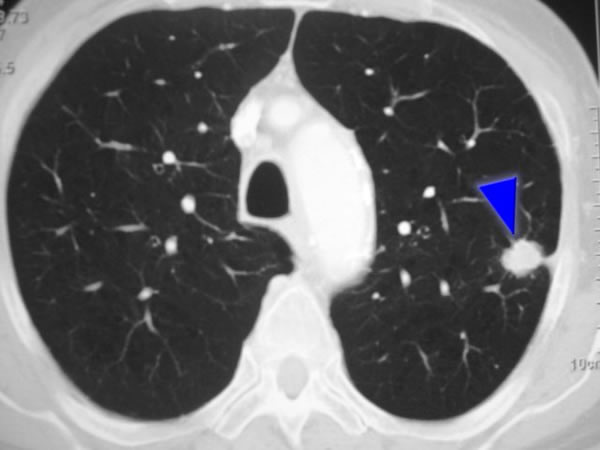

El molgramostim inhalado una vez al día produjo un mayor aumento de la transferencia de gas pulmonar que el placebo en pacientes con proteinosis alveolar pulmonar autoinmune (PAPa), una enfermedad rara que se caracteriza por la acumulación progresiva de surfactante e hipoxemia causada por autoanticuerpos contra el factor estimulante de colonias de granulocitos y macrófagos. New England Journal of Medicine, agosto de 2025.